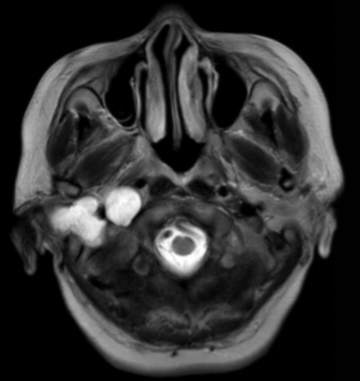

(2023-05-15 10:00,本院)行磁共振(颅脑)检查提示:右侧乳突区异常信号,考虑恶性、软骨来源肿瘤,软骨肉瘤可能性大。(集体讨论意见);脑内散在多发缺血灶。

(2023-05-12 10:15,本院)行CT(颅脑)检查提示:右侧颞骨广泛骨质破坏,伴巨大软组织肿块,性质待定,考虑肿瘤性病变,颈静脉球瘤?软骨源性肿瘤?请结合临床及病理进一步明确。

术后复查MRI: